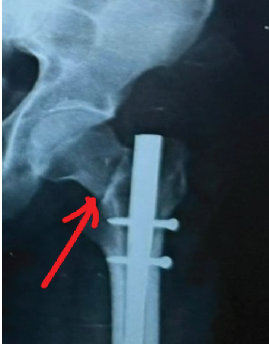

The Impact of Medial Cortical Reduction on the Outcomes of Fixation in Unstable Intertrochanteric Fractures

Parimal Vairagade , Devashish Barick , Sushil Mankar , Aniruddha Vaidya , Vaibhav Panchbhai

………………………………p.545-552